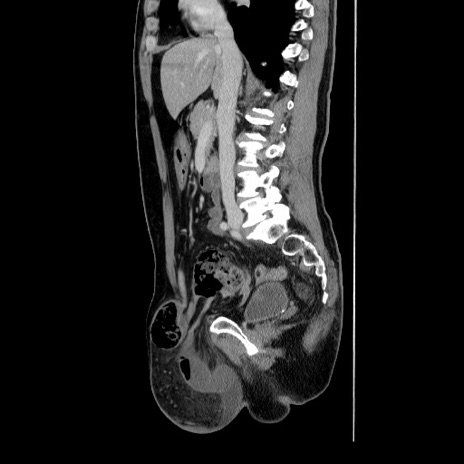

症例34(矢状断像)

【症例】60歳代 男性

【主訴】右鼠径部膨隆

【現病歴】1年程前より右鼠径部膨隆あり。自己にて還納可能だったため放置していた。3時間前より右鼠径部の脱出を認め、還納困難となり受診。

【身体所見】右鼠径部に小児頭大の膨隆あり。弾性硬であり、用手還納は困難。左鼠径部にも膨隆を認める。脱出はなし。